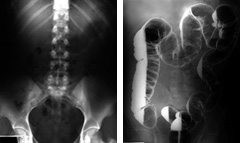

The radiograph on the left is a plain film of the abdomen.

The radiograph on the right is the same, except the large intestine is filled with barium and air. For this particular film, the patient was lying on his side, which is why the barium (white) looks like it is standing in vertical columns.